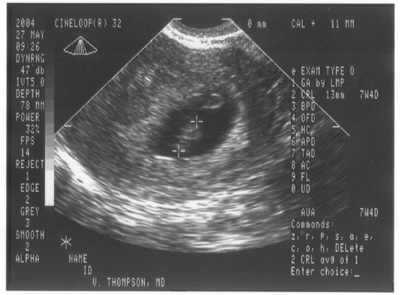

27. Mai 2004